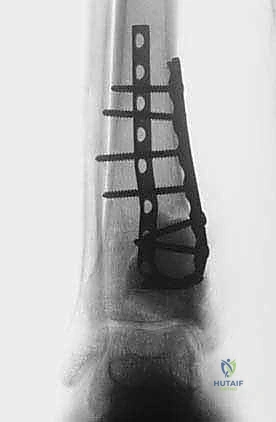

الخطوة الخامسة: إعادة البناء والترميم (Reconstruction)

بعد القضاء على الورم، يتبقى تجويف فارغ داخل العظم. يقوم الدكتور هطيف بملء هذا الفراغ إما باستخدام ترقيع عظمي (Bone Graft) أو الإسمنت العظمي (PMMA - Bone Cement). الإسمنت العظمي له فائدة مزدوجة: فهو يوفر دعماً ميكانيكياً فورياً للعظم، والحرارة الناتجة عن تصلبه توفر تأثيراً إضافياً قاتلاً للخلايا الورمية المتبقية.